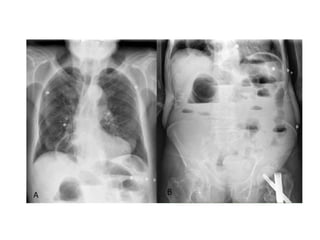

El diagnóstico seconfirma mediante estudios radiológicos SERIE ABDOMINAL Rx abdomen paciente en posición supina Rx tórax Rx abdomen con enfermo de pie SENSIBILIDAD DEL 70 AL 80%

• La triadaclásica de obstrucción en el examen radiológico es: o Asas de intestino delgado dilatadas (mayores a 3 cm) o Niveles hidroaéreos o Ausencia de aire distal

Signo del “granode café” Hallazgo clásico y diagnóstico del vólvulo sigmoideo en una radiografía simple de abdomen